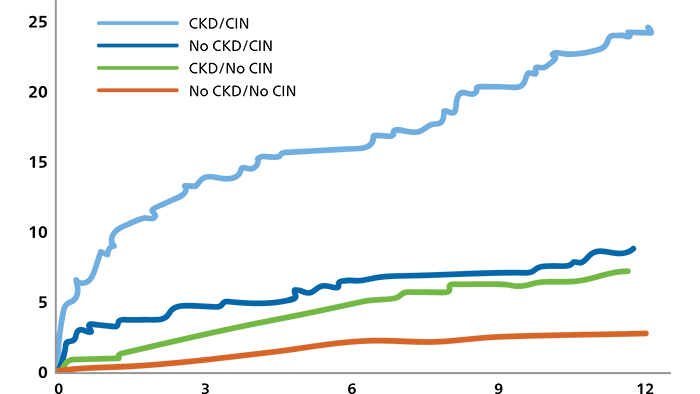

Mortality significantly increases at 1-year with CKD and CIN10

Expand each product to learn more.